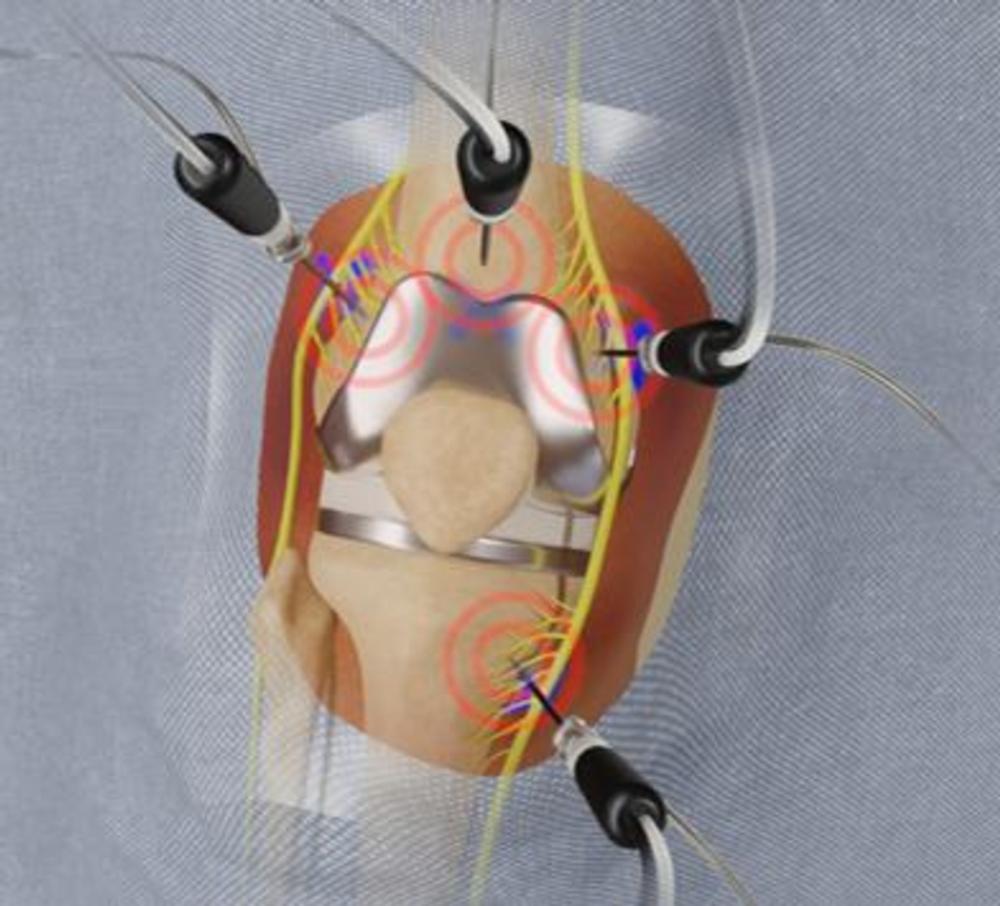

A procedure called cooled radiofrequency ablation (C-RFA) offers hope for these patients. The procedure involves insertion of an introducer needle around the knee under local anesthesia targeting specific nerve locations. A probe is then guided through the introducers. The tip of the probe imparts a low voltage current (radiofrequency) to the deep sensory nerves around the knee. Water circulating through the system allows for a greater dissipation of heat from the tip of the probe.

Figure 1. Radiofrequency ablation electrode is placed into the introducer needle after the placement of the introducer needle. Positioning was verified with imaging.

Figure 2. Radiofrequency ablation electrode is placed into the introducer needle after the placement of the introducer needle. Positioning was verified with imaging.

Figure 8. Image of the four needle target points.

Figure 9. Cooled radiofrequency ablation technique.

Figure 10. Cooled radiofrequency ablation technique.